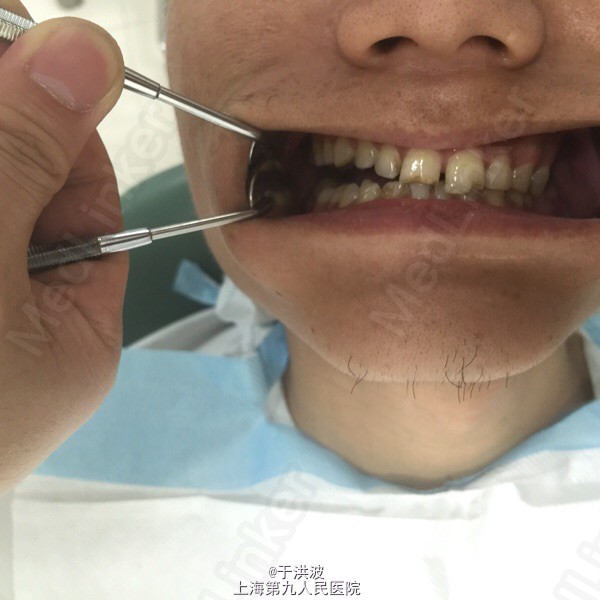

男性,28岁。右侧上颌牙齿松动无法咬合4月余。

面部基本对称,右侧面部无明显膨胧,无压痛。口内右侧上颌前庭沟黏膜无异常,右侧上颌牙列松动,牙列上移,与下颌牙无咬合接触。CT示右侧上颌骨弥散性吸收。血常规未见异常